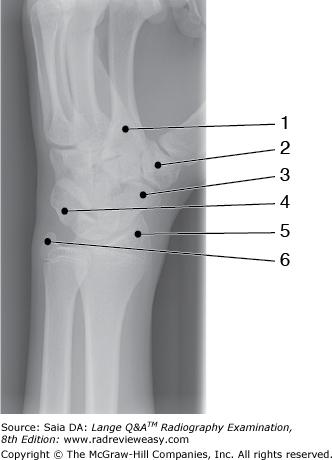

Which of the following correctly identifies the radial styloid process in the illustration in Figure A?

D Number 11

-An anterior view of the forearm is pictured. The proximal anterior surface of the ulna (number 8) presents a rather large pointed process at the anterior margin of the semilunar (trochlear) notch (5) called the coronoid process (6). The olecranon process is identified as number 4, and the radial notch of the ulna is number 7. Distally, the ulnar head is number 9, and the styloid process is labeled 10. The radius (number 12) is the lateral bone of the forearm. The radial head is number 3, the radial neck is number 2, and the radial tuberosity is number 1. Distally, the radial styloid process is labeled 11.